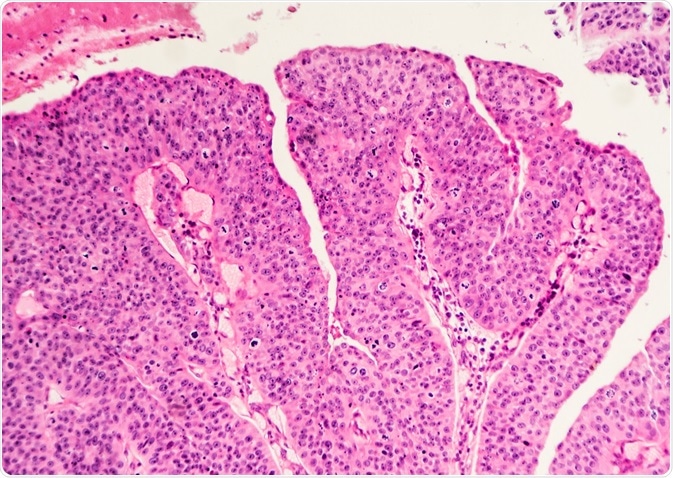

Bladder Cancer Histopathology

Image Credit: David Litman / Shutterstock

Histopathology provides a vast amount of valuable information about bladder cancer, such as the type, stage and grade of the cancer. This enables doctors to assess patient prognosis, best treatment options and possible specific therapies.